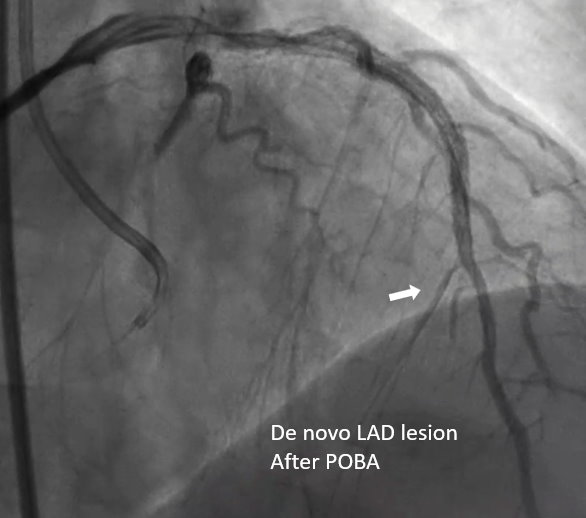

The patient received primary percutaneous coronary intervention (PCI) with balloon angioplasty (POBA) and a drug-eluted stent (DES) for middle LAD. Three days later he underwent staged PCI for RCA. After wire externalization via rendezvous technique, the patient developed acute angina, diaphoresis, and hypotension. Angiogram found a de-novo LAD lesion just distal to the stent.

During the staged PCI, antegrade approach with escalating guidewires ended up in subintimal space; retrograde approach from the first LAD-septal branch failed because there was difficulty crossing the existing mid-LAD stent. Further attempts from the third septal branch successfully reached the distal cap of the CTO via proximal descending artery, finally entering the antegrade guide extension catheter by rendezvous technique. After wire externalization and POBA for RCA, the patient became agitated from acute angina, diaphoresis and hypotension. Angiogram of LAD found an acute de novo LAD lesion adjacent to the distal stent edge, leaving only TIMI-1 flow. We stopped the RCA procedure and wired LAD, performed POBA at the de novo LAD lesion and restored coronary blood flow. Then we continued PCI of RCA with POBA followed by the deployment of two DES. Final angiogram showed adequate stent expansion and TIMI-3 flow in RCA. The patient was discharged with no further complications. Follow-up echocardiogram three months later showed improved wall motion and ejection fraction, indicating good myocardial recovery.